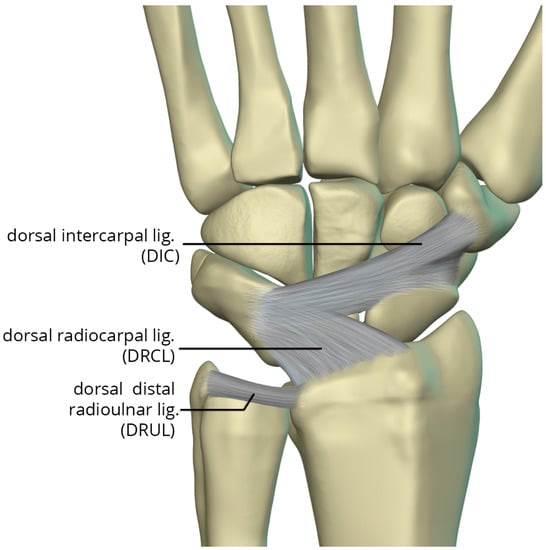

The dorsal capsular ligaments (Figure 25) include the dorsal radiocarpal ligament (DRCL) and dorsal intercarpal ligament (DIC). The dorsal radiocarpal ligament (DRCL) is also referred to as the dorsal radiotriquetral ligament [26]. The DRCL extends from the dorsal rim of the radius, between Lister tubercle and the sigmoid notch, to the dorsal triquetrum. This ligament has fibers continuous with the fourth and fifth extensor compartment septa. Variants of this ligament include various additional bands, one of which may cover the dorsal aspect of the proximal scaphoid. The dorsal intercarpal ligament (DIC) is also sometimes referred to as the dorsal scaphotriquetral ligament due to its attachments. The DIC ligament extends from the dorsal ridge of the triquetrum to the dorsal groove of the scaphoid and proximal rim of the dorsal aspect of the trapezium. Along its course some fibers attach to the dorsal distal lunate. The DIC ligament may have one or two distinct fascicles, and sporadically has fibers extending to the trapezoid and capitate.

Figure 25. Illustration of the dorsal capsular ligaments: the dorsal radiocarpal ligament and dorsal intercarpal ligament.